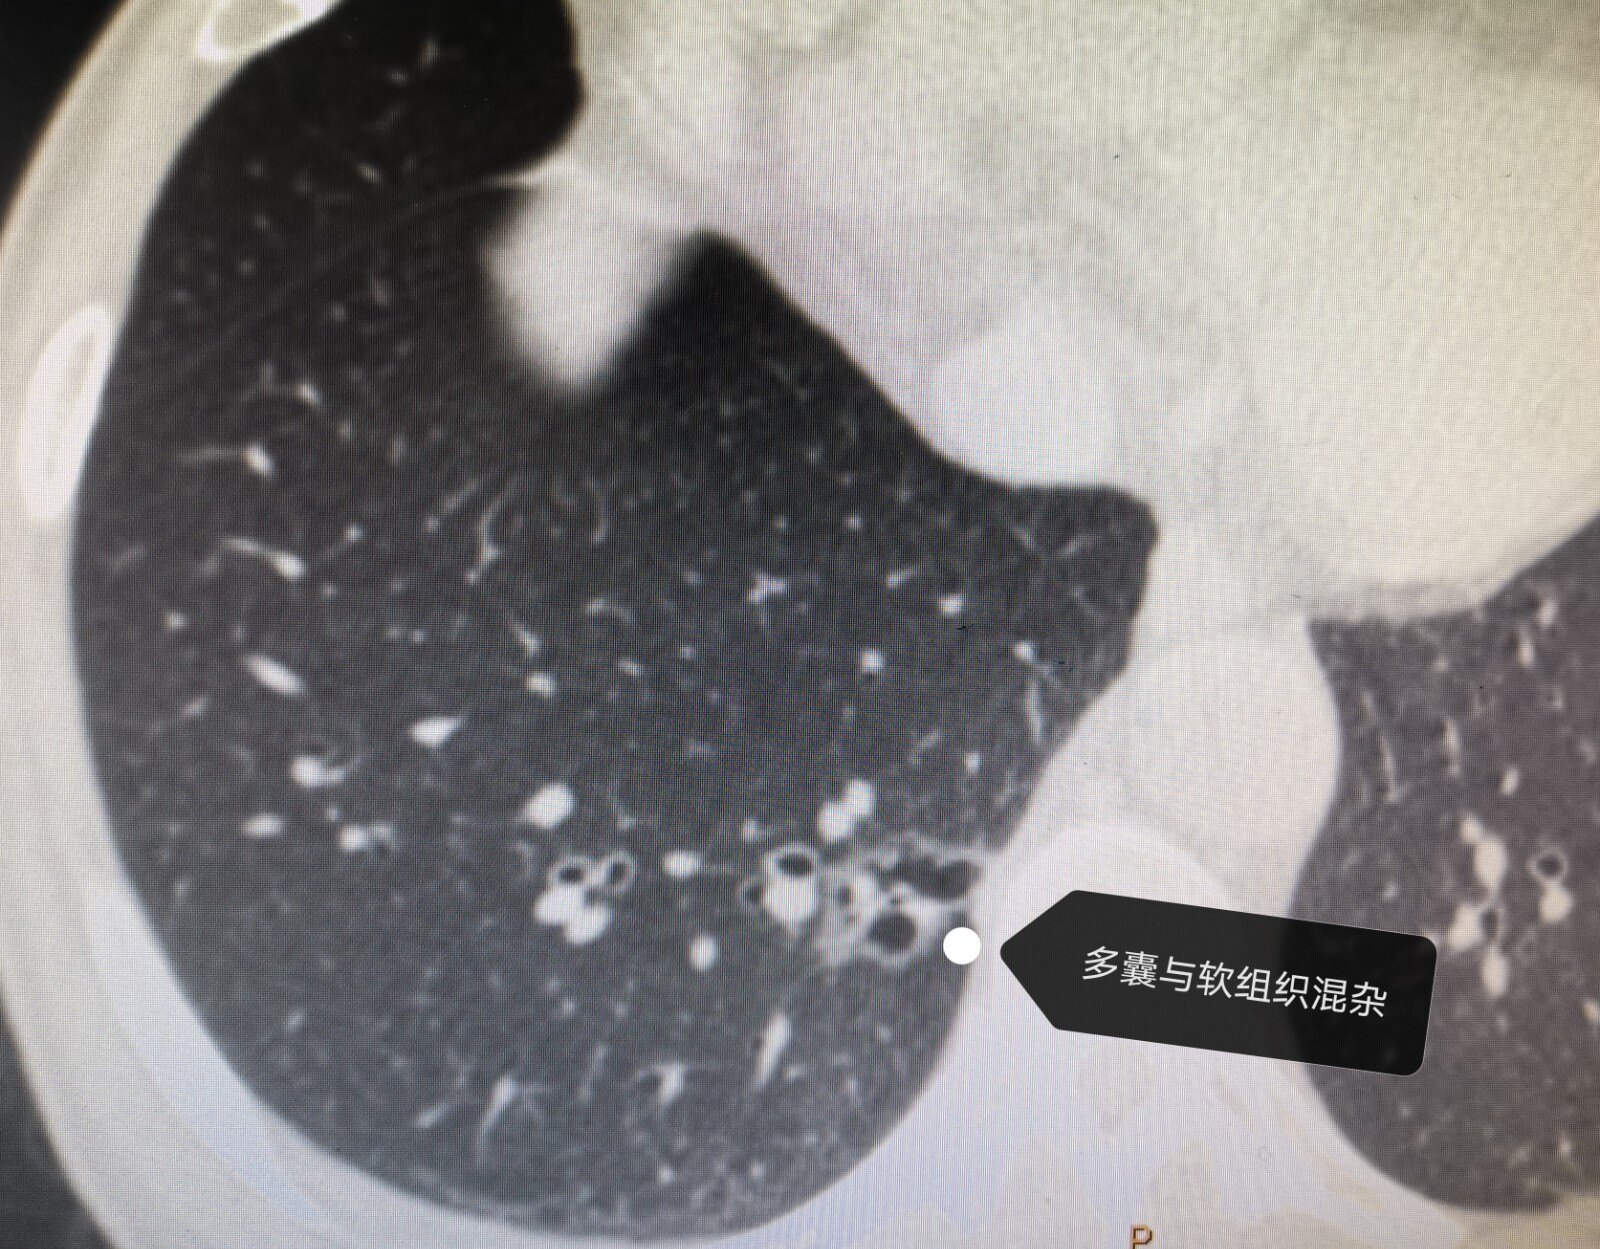

【病例讨论】双肺弥漫囊状空泡(有图)请教各位专家 [病例帖]